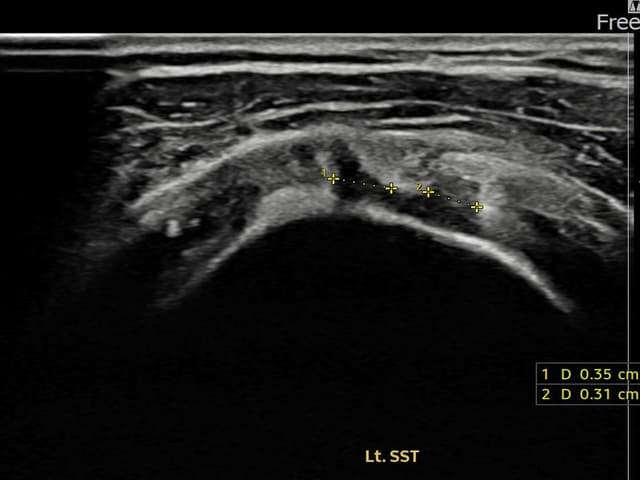

[촬영시기:24.01.08~24.03.14]

[어깨인대 축소봉합술] 좌측 어깨 통증으로 팔을 올리기 불편하여 내원하셨습니다.